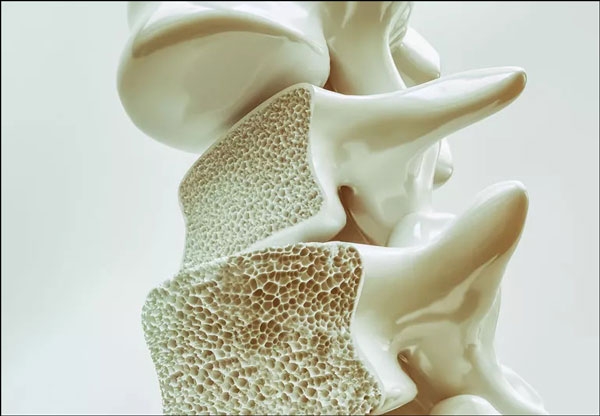

قد تظنُّون أنَّ كلمة هشاشة العظام تعبير مبالغ فيه، ولكن للأسف، في بعض الأحيان وبسبب ظروف معينة تكون العظام هشة كقطعة بسكويت، وفي هذا المقال سوف نتحدث عن هشاشة العظام وأسبابها، ودور الحليب في الوقاية منها.

ما هي هشاشة العظام؟

هشاشة العظام، والمعروفة أيضاً باسم ترقُّق العظام، هي حالة تضعف فيها العظام وتصبح أكثر عرضة للكسور، وتُعدُّ هذه الحالة من أكثر أمراض العظام شيوعاً، خاصةً عند النساء بعد سن اليأس.

أسباب هشاشة العظام:

تحدُث هشاشة العظام عندما يخسر الجسم من كثافة العظام، ويكون سبب ذلك: